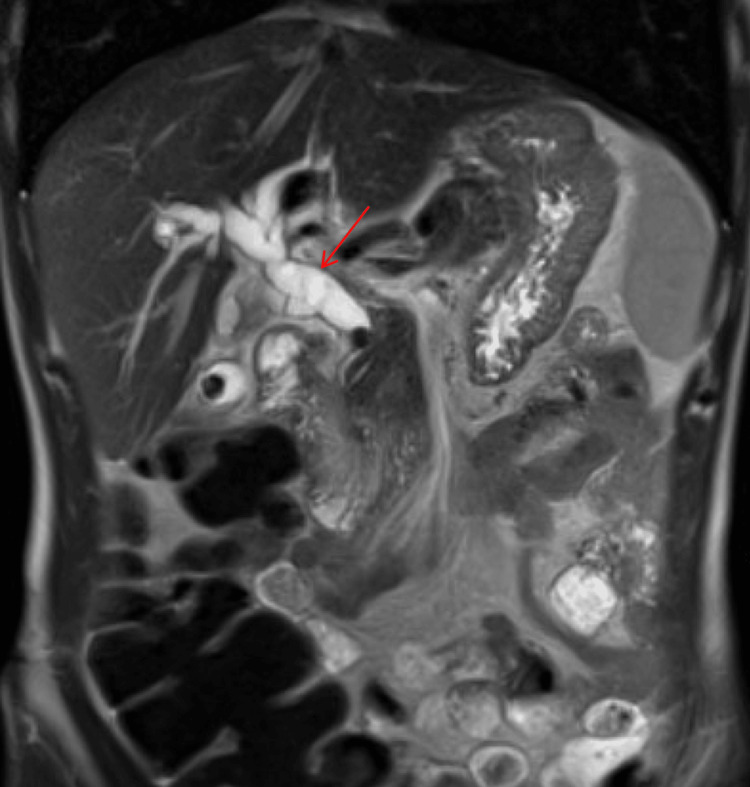

An MRCP demonstrated choledocholithiasis within the distal common bile duct (CBD) with significant intra and extrahepatic ductal dilation (Figure 2). He underwent an endoscopic retrograde cholangiopancreatography with sphincterotomy. Multiple stones were removed; however, due to concern for residual retained stones, a 10 French fully covered metal endobiliary stent was placed (Figure 3). A prophylactic plastic endopancreatic stent was also placed in the dorsal pancreatic duct due to incidental cannulation.